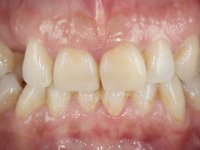

Female patient, 43 years old, non-smoker. Showed an edentulous space in the upper right canine area, resulting from tooth 1.3 impaction. The space had a mesio-distal diameter reduced to the normal size of the upper canine. This is consistent with the presence in the arch of the deciduous canine up to two years ago). Orthopantomography allows clearly view of tooth 1.3 impaction.The patient has a thick gingival phenotype and tolerable oral hygiene.

The proposed treatment results from the limitations imposed by the patient, who refused an orthodontical pull of the canine into the edntulous space, and was unwilling to extract the impacted canine and place an implant in the zone of 1.3. Thus, the confection of a Maryland Bridge was proposed, with a Zr infrastructure and two retainers. The mesial retainer would be bonded to the palatal face of the tooth 1.2 and the distal retainer was to be bonded to the palatal wall of tooth 1.4.

To define the dental zone to be covered by the Maryland bridge retainers, the patient was asked to perform maximum intercuspidation movements, and the contact points were marked with articular paper. Tooth preparation of the interproximal surfaces was made, to create a prosthetic insertion axis. It was sought that the mesio-distal diameter at the incisal level was equal to the diameter mesio-distal at the cervical level, that is to say, the interproximal walls were parallelized. Tooth preparation was done with fine grain diamond drills, and later polishing was done with abrasive discs. Color information was collected even before confection of the impression, to avoid dehydration of the arcade. Definitive impression was made using wash technique impression with silicone of heavy and regular consistency, both with fast setting, and a working plaster model was prepared in the lab. A laboratory scanner was used to scan the working model, and later, the infrastructure for the Maryland bridge was made using a CAD-CAM process. Ceramic was placed on this subframe. A ceramic adhesive was applied to the internal surface of the wings and connectors, which would enable bonding to the adjacent teeth. The adhesive bridge was bonded in the mouth following the conventional bonding technique. After bonding, the protrusion and laterality movements were carefully checked to avoid undesirable contacts.